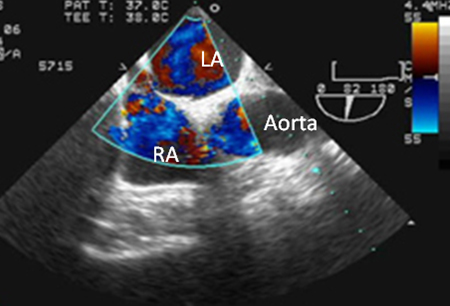

pfo echocardiography sale